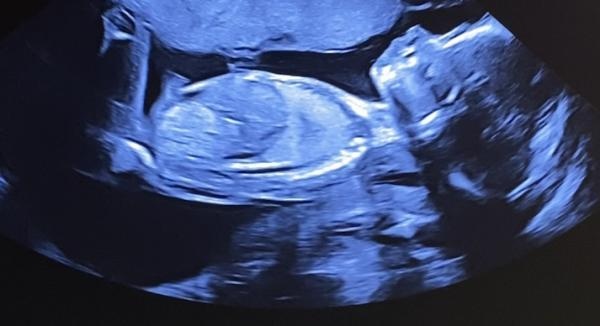

Fick höra på RUL att det är en flicka, men hört så många som fått fel kön. Kan man vara säker på att detta är en flicka?

Det är svårt att säga på dessa bilderna för jag ser inte direkt en tydlig nubb/könet.

Det är svårt att se.